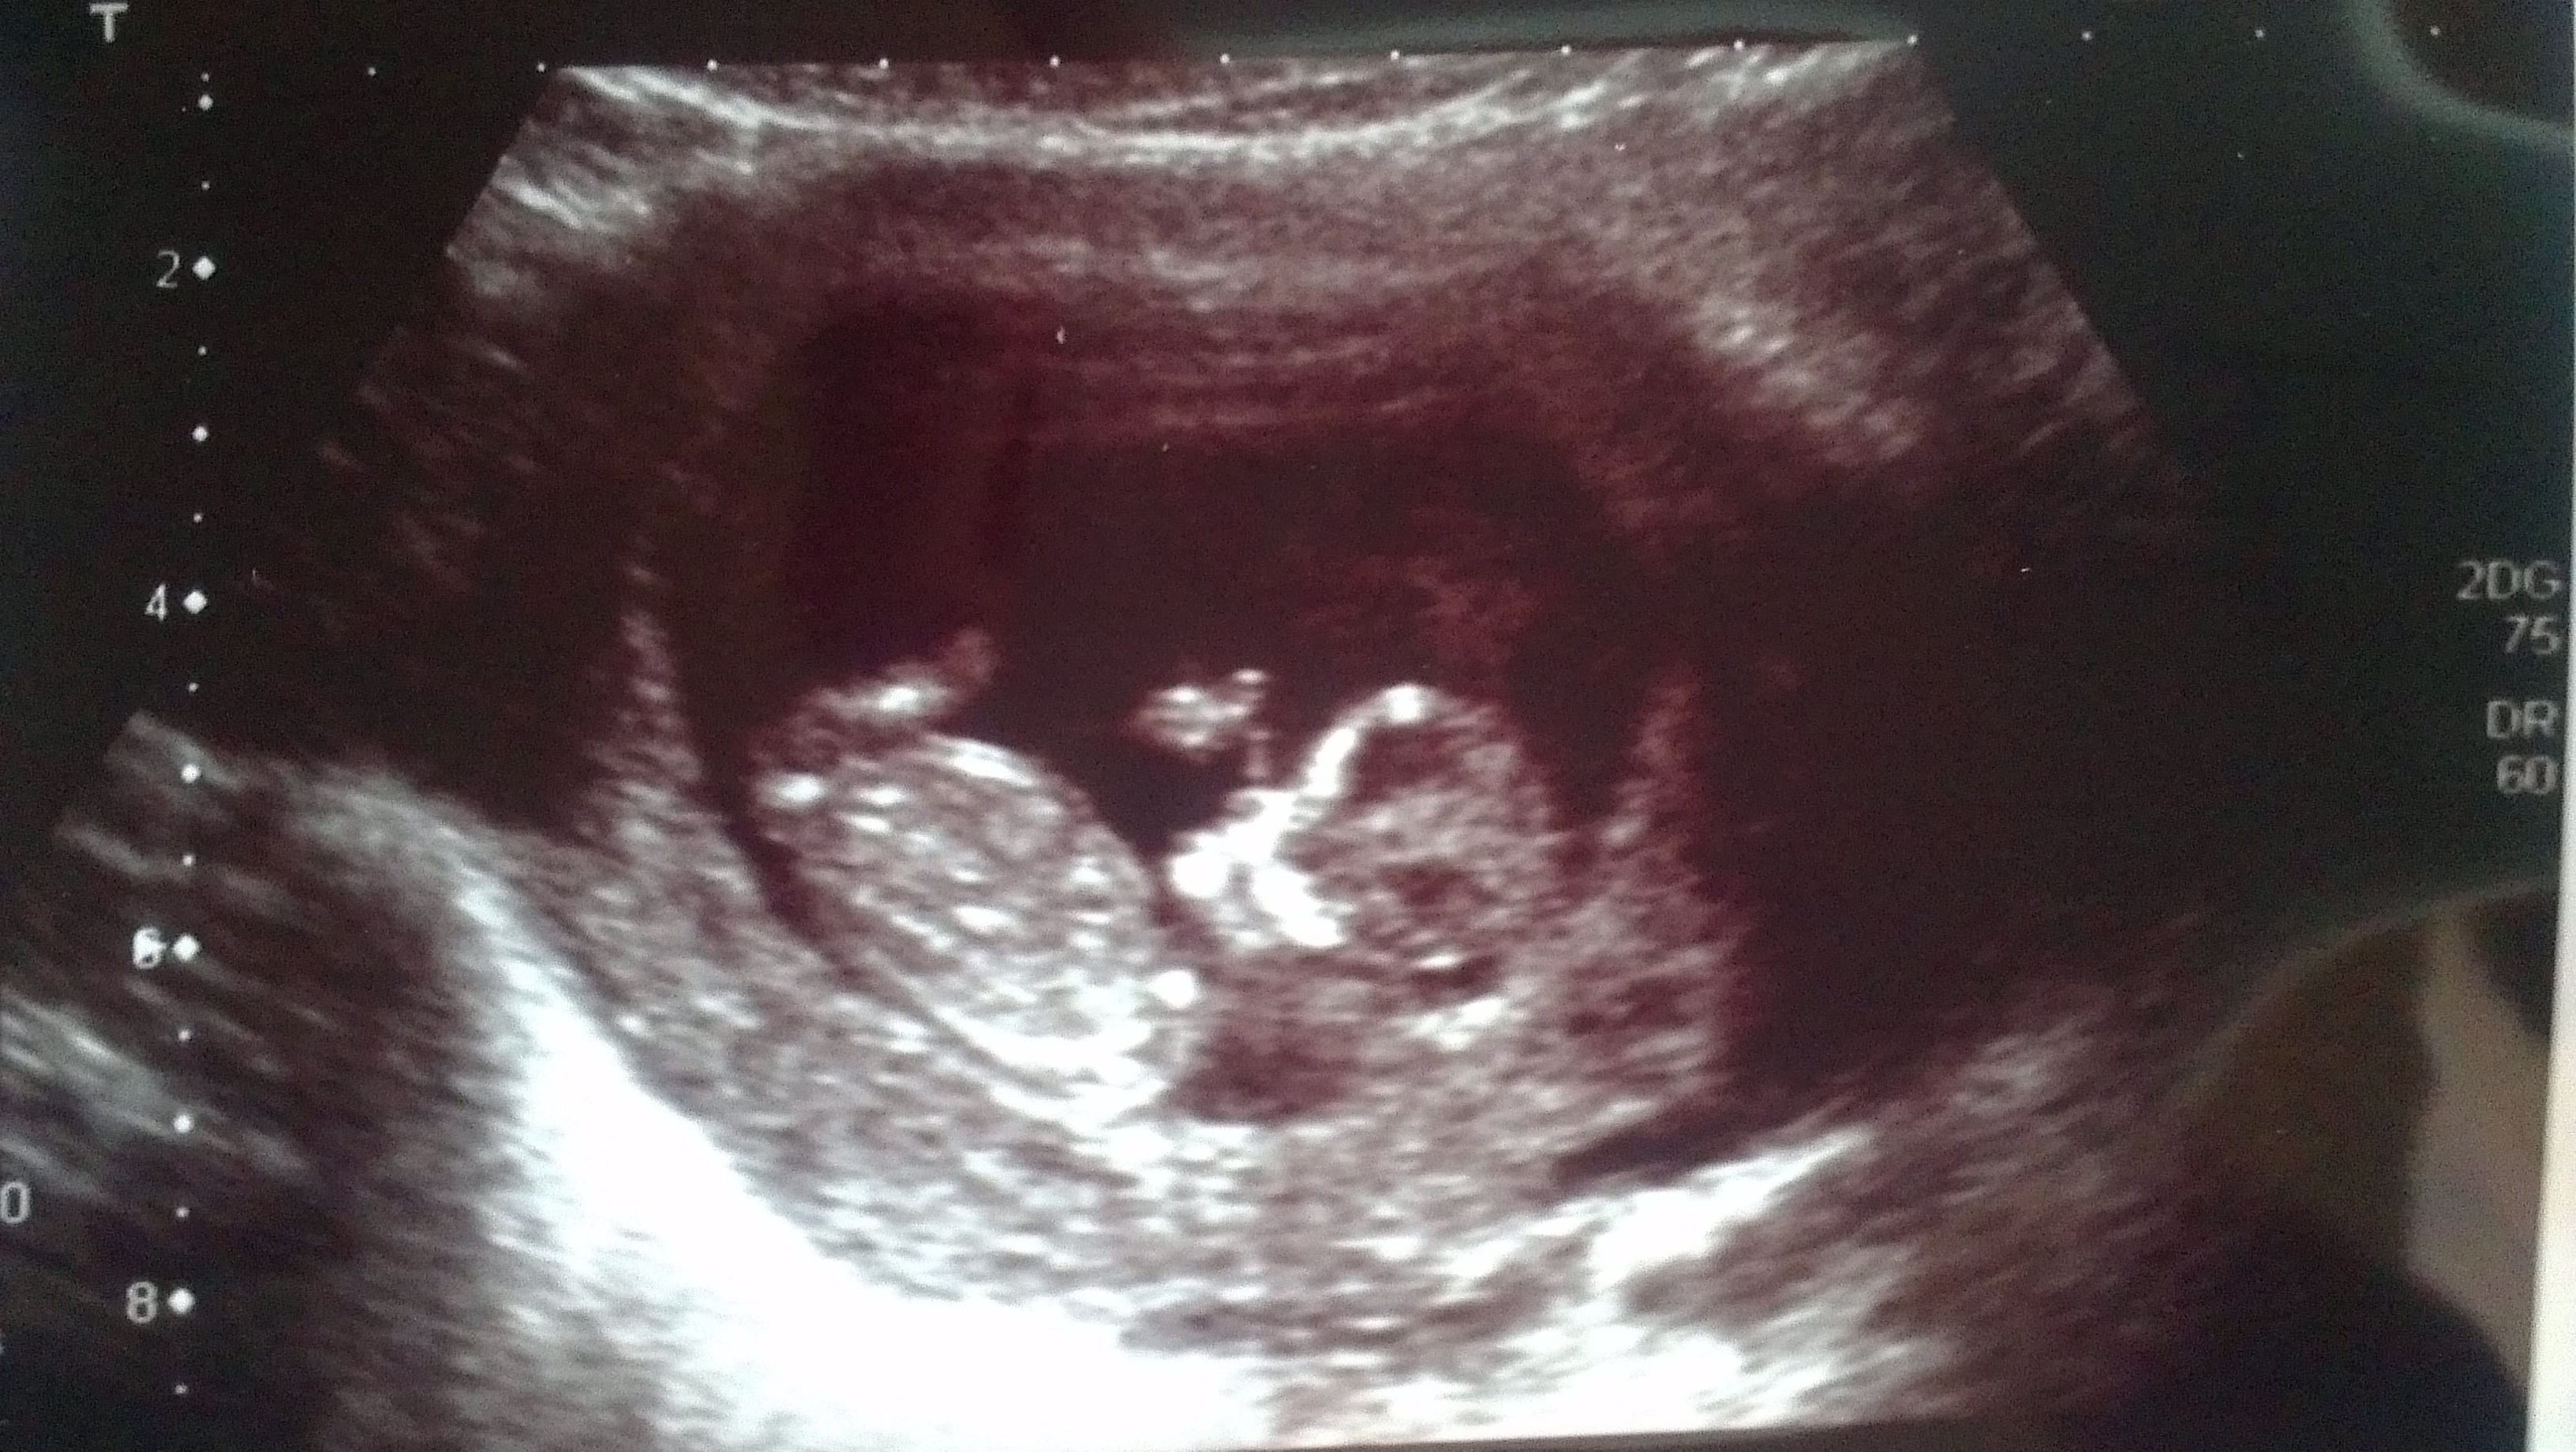

Have had gender scan but looking for more help!

Any more pics like potty shots? Id guess boy from skull, its the only clue i can see.

I don't see a nub here.

No clues in this pic.